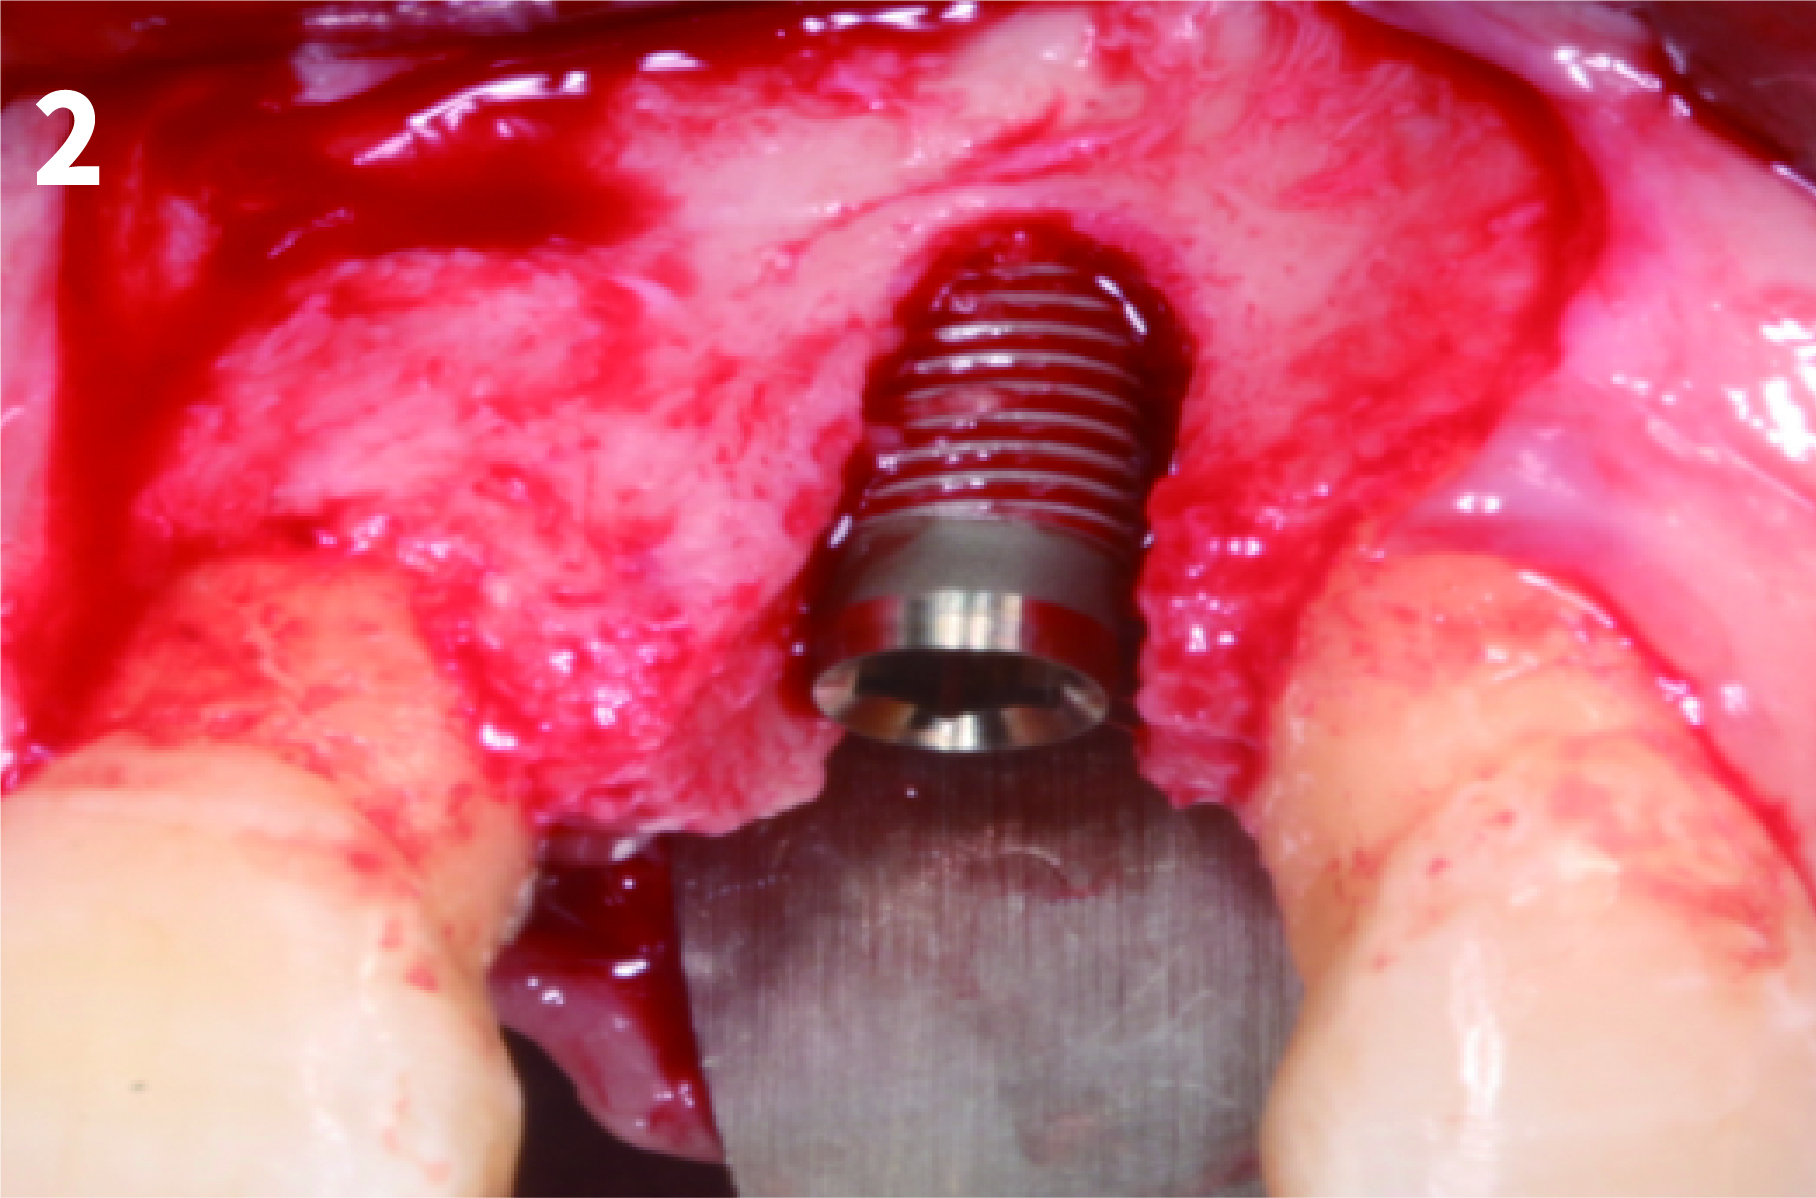

Case 1: Simply Augmented Severe Dehiscence Defect on Anterior Area